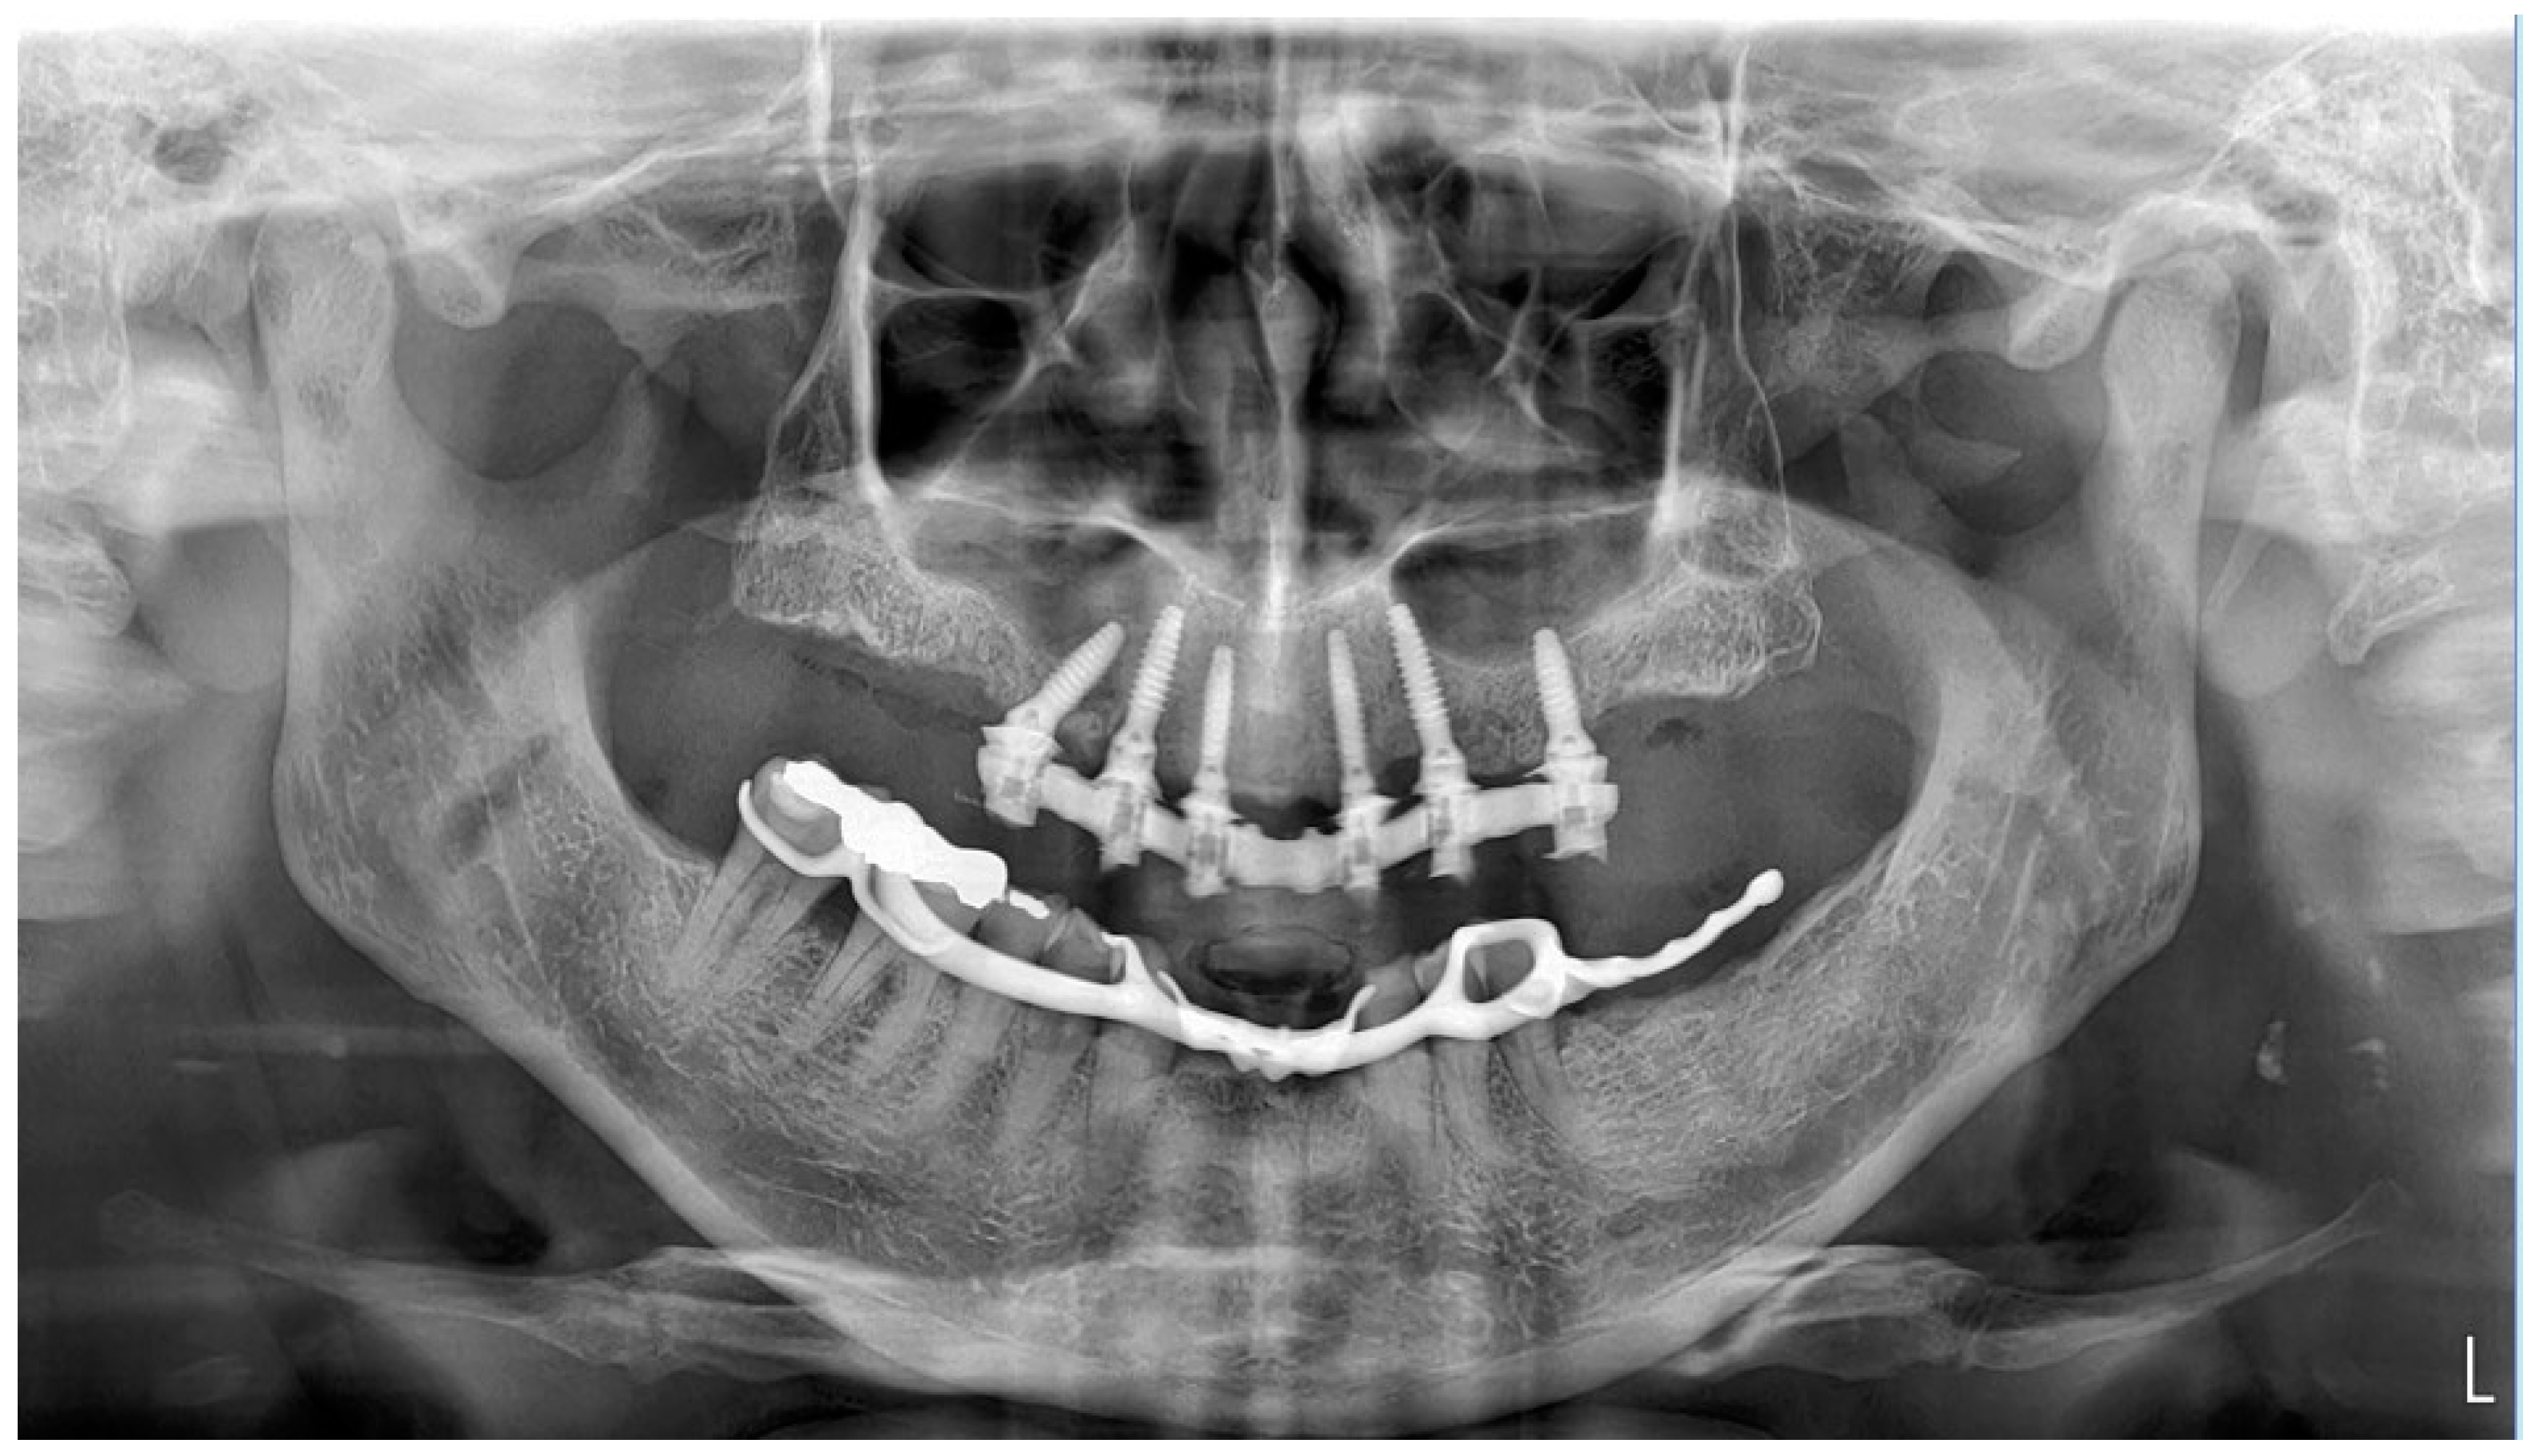

2. Materials and Methods

2.2. Surgery

3. Results